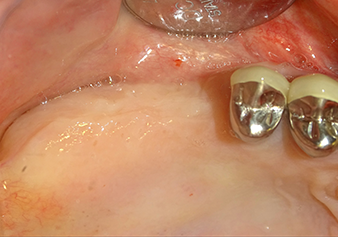

A 49-year-old female patient, a non-smoker and with nothing remarkable in her general medical history, was referred to our oral surgery practice for surgical extraction of tooth 16 and subsequent implantation. After the extraction, the patient experienced mild sinusitis trouble with the resultthat we initially waited six months before carrying out the measure. The residual bone height at the planned implant position measured 3-4 mm (Fig. 1 and 2).

Following an intermediate check (Fig. 4) a further preparation step was performed (Fig. 5). Afterwards, the hydraulic Z35P instrument was used to lift the membrane to the desired position (Fig. 6 and 7). This was followed by further piezosurgical preparation of the implant bed, concluded with a rotary bur and shoulder milling cutter up to the implant diameter of 4.8 mm. Before the implant was inserted, the augmentation material (particle size approx. 0.8-1.6 mm) was introduced underneath the Schneiderian membrane (Fig. 8).

To move the augmentation material in the direction of the maxillary sinus atraumatically, the implant was inserted very slowly by hand (Fig. 9). In the process, the membrane was pushed in the cranial direction once again. After two months, the surgical site healed without irritation. Six months later, the x-ray check showed a significant increase in opacity as an indication of ossification (Fig. 10). The prosthetic restoration was carried out with a metal-ceramic crown.